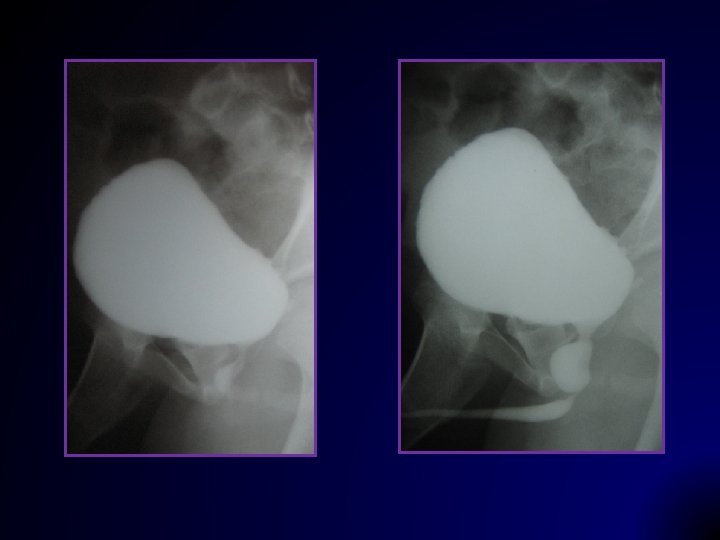

VCUG Kurallara uygun olmalı

Sınıflama (IRSC, 1985) Reflü derecesi ile yaş, doğal gidiş / tedavi seçiminde önemli